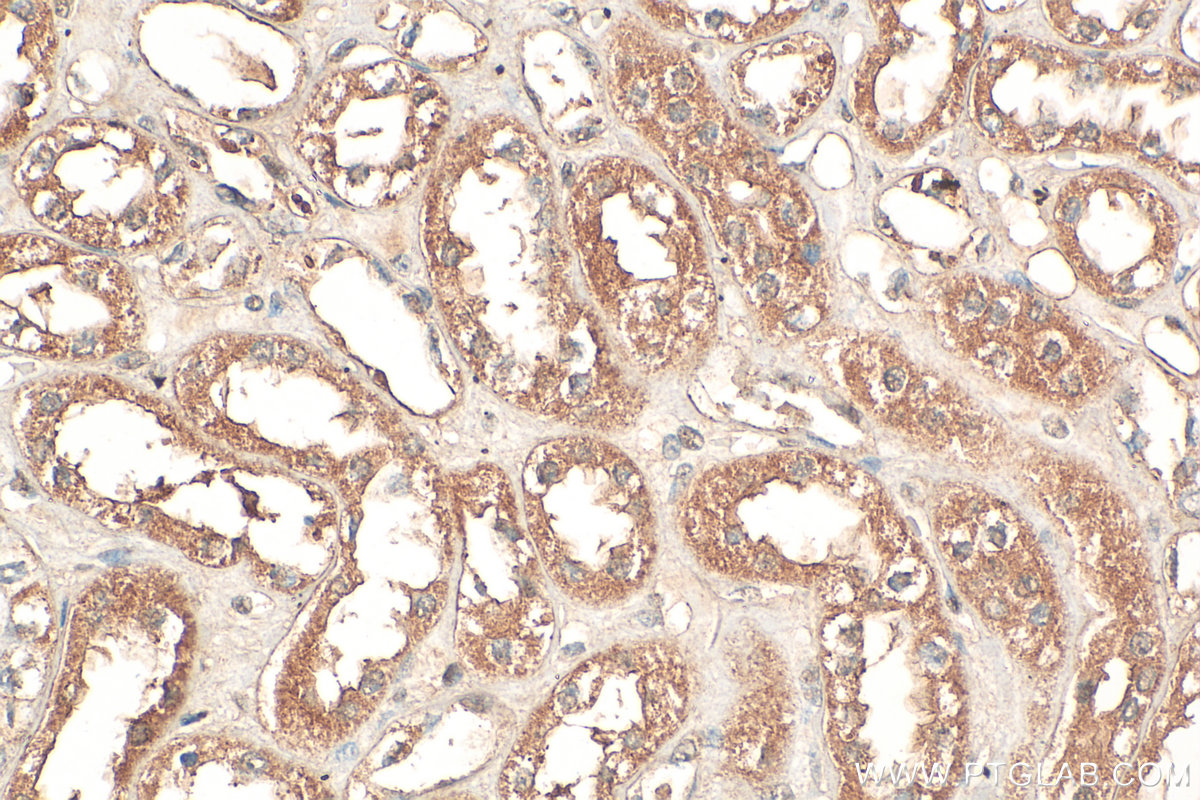

| Positive IHC detected in | human colon tissue, human kidney tissue Note: suggested antigen retrieval with TE buffer pH 9.0; (*) Alternatively, antigen retrieval may be performed with citrate buffer pH 6.0 |

| Immunohistochemistry (IHC) | IHC : 1:50-1:500 |